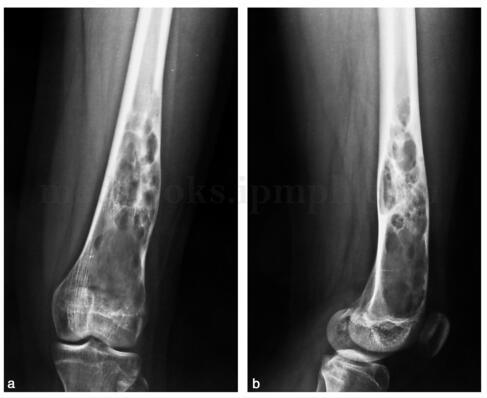

动脉瘤样骨囊肿(abc)

动脉瘤样骨囊肿影像

动脉瘤样骨囊肿图片

动脉瘤样骨囊肿ct表现

胫骨动脉瘤样骨囊肿